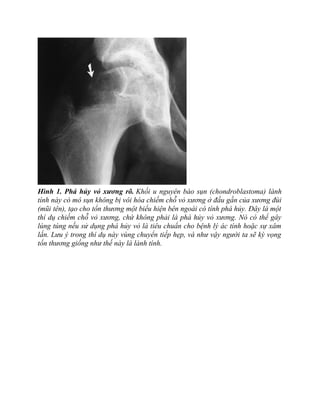

Hình 1. Phá hủy vỏ xương rõ. Khối u nguyên bào sụn (chondroblastoma) lành

tính này có mô sụn không bị vôi hóa chiếm chỗ vỏ xương ở đầu gần của xương đùi

(mũi tên), tạo cho tổn thương một biểu hiện bên ngoài có tính phá hủy. Đây là một

thí dụ chiếm chỗ vỏ xương, chứ không phải là phá hủy vỏ xương. Nó có thể gây

lúng túng nếu sử dụng phá hủy vỏ là tiêu chuẩn cho bệnh lý ác tính hoặc sự xâm

lấn. Lưu ý trong thí dụ này vùng chuyển tiếp hẹp, và như vậy người ta sẽ kỳ vọng

tổn thương giống như thế này là lành tính.